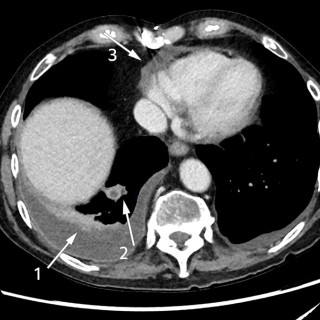

En jente i tenårene ble innlagt ved barneavdelingen grunnet kjevesperre, hevelse på halsen og mistanke om peritonsillær abscess. Utredningen skulle avdekke et mer komplekst symptombilde enn forventet ut fra innleggelsesårsak. En ung jente, fra tidligere vesentlig frisk foruten pollenallergi, ble innlagt etter to ukers sykehistorie med halssmerter. Hun var tidlig i forløpet vurdert hos fastlegen, der hurtigtest for mononukleose (Monospot) var negativ. Tilstanden ble tolket som tonsillitt, og pasienten fikk forskrevet en kur med peroral fenoksymetylpenicillin. Grunnet svelgsmerter ble ikke...